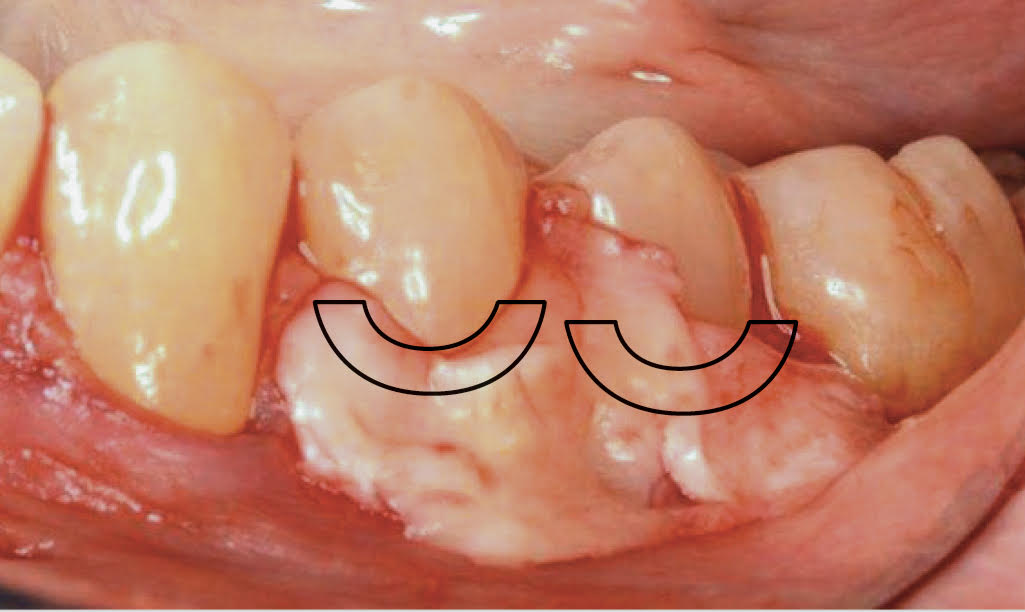

Fig 1. Miller Class I recession on tooth No. 11 (Fig 1) treated with tuberosity CTG (Fig 2). Note this CTG (which is the tuberosity CTG from Fig 5) was placed before the practitioner developed thinning techniques, so a keloid-like appearance was observed even 1 year after grafting.

Figure 1

Fig 2. Miller Class I recession on tooth No. 11 (Fig 1) treated with tuberosity CTG (Fig 2). Note this CTG (which is the tuberosity CTG from Fig 5) was placed before the practitioner developed thinning techniques, so a keloid-like appearance was observed even 1 year after grafting.

A complication in using CT from the tuberosity reported in the literature is a tendency for clinicians to harvest tissue that is too thick.12 This can result in a keloid-like appearance similar to what may occur with an EPG. This excess thickness can be unesthetic (Figure 1 and Figure 2) and subsequently require a gingivoplasty to remove the superfluous tissue.12 This problem may perhaps be alleviated with proper thinning of the graft prior to insertion into the recipient area.

Fig 5. Pre- (Fig 5) and post- (Fig 6) DGV procedure. Note the 7-mm pocket distal to tooth No. 15 before treatment and normal probing depth after treatment. It would have been easier for the restorative dentist to place this crown with increased tooth structure if the tuberosity tissue had been removed previously.